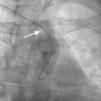

Case reportA 44-year-old man presented with several weeks of palpitations. He also described symptoms of dyspnea with mild exertion and substernal chest discomfort at rest. He had a history of long-standing systemic hypertension. The 12-lead ECG showed atrial fibrillation with rapid ventricular rate. His 2D Doppler echocardiogram revealed a mildly enlarged RA and right ventricle (RV). He subsequently underwent right and left heart catheterization with selective coronary angiography. Right and left heart catheterization with a full oximetry run to calculate shunts revealed Qp/Qs of 1.3. Selective coronary angiography was performed using right radial artery access, and showed no significant coronary disease. However, angiography of the aortic arch showed a single trunk takeoff for the large vessels from the aortic arch (Figure 1). Using right femoral vein access, a 5-Fr multipurpose diagnostic catheter was advanced into the upper (Figure 2) and middle (Figure 3) right pulmonary veins as they opened into the superior vena cava (SVC). To exclude any possible associated atrial septal defect, an MP-1 catheter was engaged into what proved to be a coronary-cameral fistula (CCF) opening into the RA separately from the coronary sinus (Figure 4), the CCF went from the coronary vein to the RA and the coronary sinus was also filled with contrast retrogradely from the vein (Figure 4). Pulmonary angiography using a 5-Fr pigtail catheter showed a moderately dilated pulmonary trunk (Figure 5). Following consultations with the cardiothoracic surgery and pediatric cardiology teams, it was felt that the best course of management would be to follow the patient clinically with serial echocardiography, as there was no significant right-to-left shunt.

The most common aortic arch branching pattern in humans consists of three great vessels originating from the arch of the aorta: the innominate, left common carotid and left subclavian arteries. In “bovine” aortic arch, rather than arising directly from the aortic arch as a separate branch, the left common carotid artery origin is moved to the right and merges with the origin of the innominate artery, or the left common carotid artery originates directly from the innominate artery rather than as a common trunk. A single brachiocephalic trunk originating from the aortic arch and then dividing into right and left brachiocephalic trunks or trifurcating to brachiocephalic, left common carotid and subclavian artery is a very rare anomaly, with few cases reported in the literature,10,11 and there is no previously reported case of SS with this anomaly.